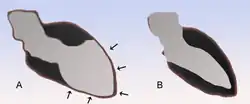

| Schematic representation of cardiomyopathy (A) compared to a normal heart (B) | |

The name "takotsubo" comes from the Japanese word takotsubo (蛸壷) "octopus trap", because when affected by this condition, the left ventricle of the heart takes on a shape resembling the round jar used for catching lobsters and octopuses.[13]

The typical presentation of takotsubo cardiomyopathy is chest pain with or without shortness of breath and associated electrocardiogram (ECG) changes mimicking a myocardial infarction of the anterior wall. During the course of evaluation of the patient, a bulging out of the left ventricular apex with a hypercontractile base of the left ventricle is often noted. It is the hallmark bulging-out of the apex of the heart with preserved function of the base that earned the syndrome the name takotsubo ("octopus trap") in Japan, where it was first described.[14]

The diagnosis is made by the pathognomonic wall motion abnormalities, in which the base of the left ventricle is contracting normally or is hyperkinetic while the remainder of the left ventricle is akinetic or dyskinetic. This is accompanied by the lack of significant coronary artery disease that would explain the wall motion abnormalities. Although apical ballooning has been described classically as the angiographic manifestation of takotsubo, it has been shown that left ventricular dysfunction in this syndrome includes not only the classic apical ballooning, but also different angiographic morphologies such as mid-ventricular ballooning and, rarely, local ballooning of other segments.[1][51][52][53][54]

The ballooning patterns were classified by Shimizu et al. as takotsubo type for apical akinesia and basal hyperkinesia, reverse takotsubo for basal akinesia and apical hyperkinesia, mid-ventricular type for mid-ventricular ballooning accompanied by basal and apical hyperkinesia, and localised type for any other segmental left ventricular ballooning with clinical characteristics of takotsubo-like left ventricular dysfunction.[52]